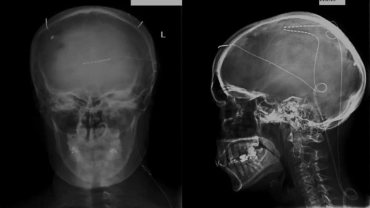

Σύγχρονες Θεραπείες

Σύγχρονη αντιμετώπιση Ν. Πάρκινσον & λοιπών κινητικών διαταραχών και πόνου